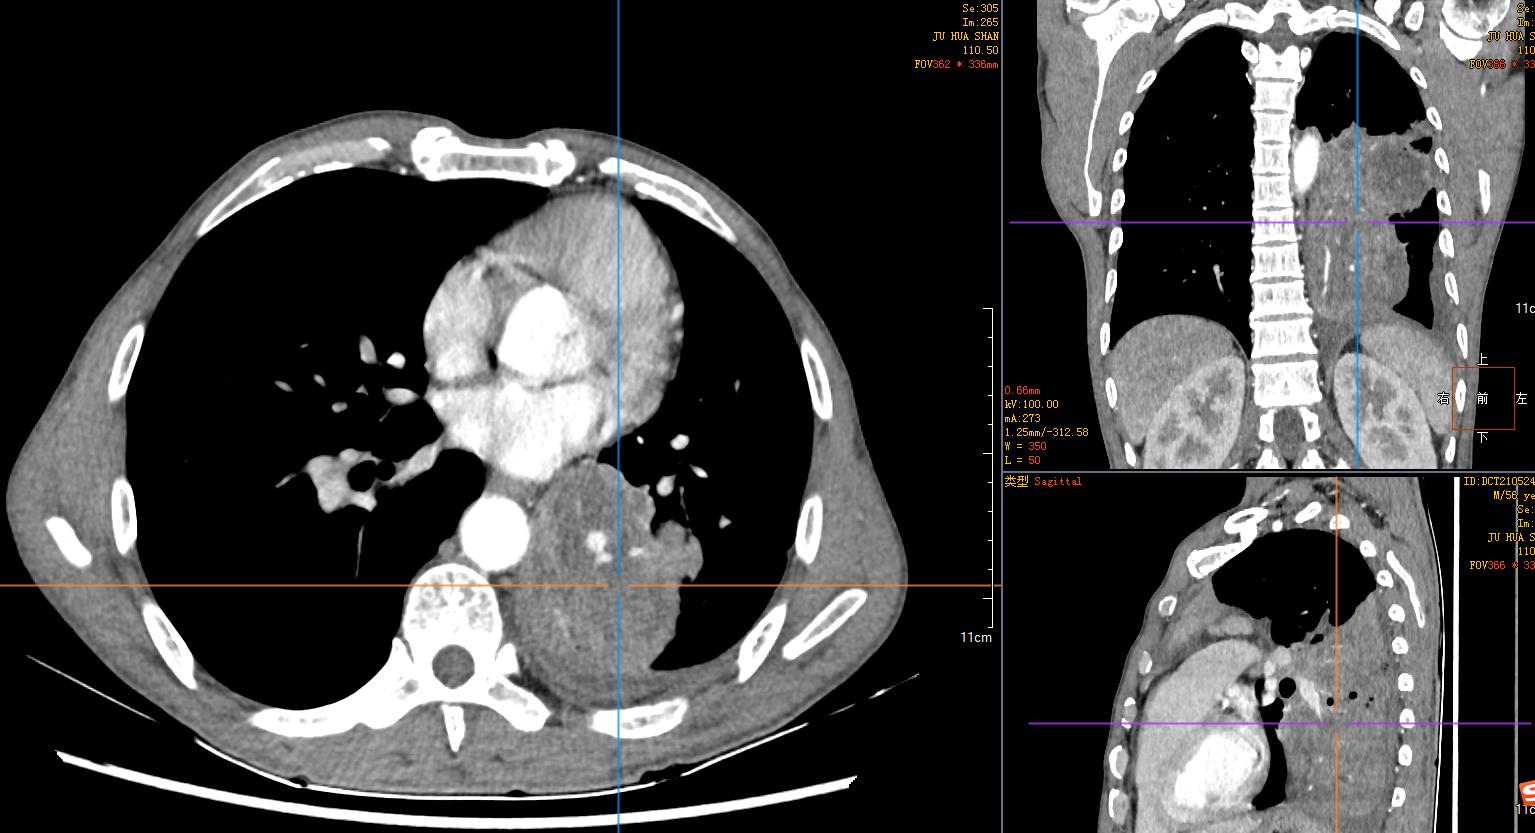

2)胸腹部平扫+增强CT示:左肺占位性肿块伴阻塞性肺不张,纵膈淋巴结肿大,建议穿刺活检。左肺动脉分支动脉瘤;右肾小错构瘤可能;双侧股骨颈小滑膜疝。